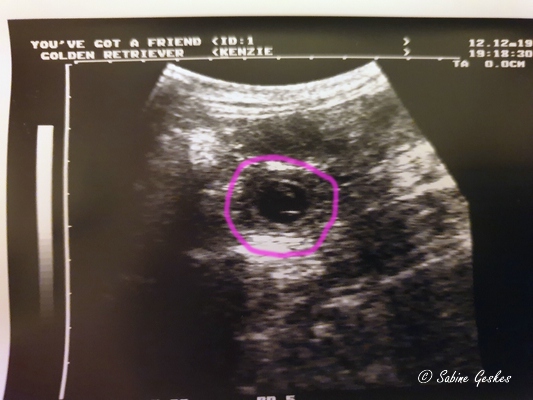

Die Spannung bis zum ersten Ultraschall ist kaum auszuhalten und natürlich haben wir schon am letzten Montag das erste Mal geschaut, ob Kenzie ein kleinen Geheimnis mit sich herumträgt. Und ja, wir haben da etwas entdeckt, was nach kleinen Fruchtanlagen aussehen könnte…. oh man, und heute (12.12.19) haben wir wieder geschaut und all unsere Hoffnungen wurden bestätigt… Wir erwarten kleine Madzies…